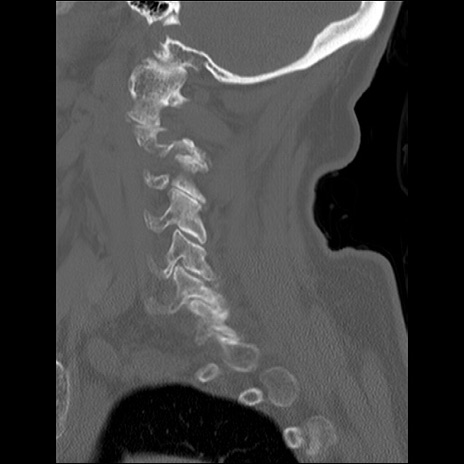

症例48 頚椎CT(矢状断像)

頚椎CT